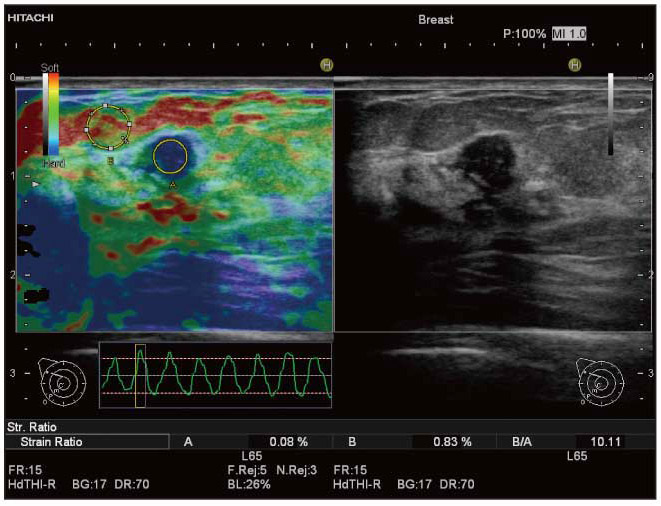

生体内の組織歪みから相対的な硬さを高速演算し,硬さ(変形)の程度をリアルタイムにカラー表示を行うことで,周囲よりも硬い部分は青く表示されます。

・Strain Ratio

Elastography画像において,任意の2か所の弾性比率を数値化します。例えば,乳腺領域では脂肪組織と関心領域の比(FLR:fat lesion ratio)を求めることができ,組織性状の研究などへの応用が可能です。